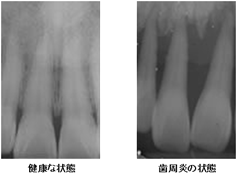

左の写真は健康な状態のレントゲン写真と歯周炎になってしまったレントゲン写真ですが、健康な状態では歯のすぐ下まで骨がしっかりとあり、歯全体を骨がしっかり支えていることがわかりますが、歯周炎になってしまうと歯根の先端まで骨が溶けてなくなってしまっているのがわかると思います。